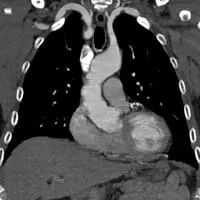

CT angiography is performed by injecting contrast into a peripheral vein, without an arterial catheter. CTA is fast, and shows excellent detail of bones and arteries. CTA requires significant radiation, and is limited in the evaluation of soft tissues, including fibrous bands and muscle anomalies. In cases of pure arterial TOS, CTA is the first-line test for many vascular surgeons.